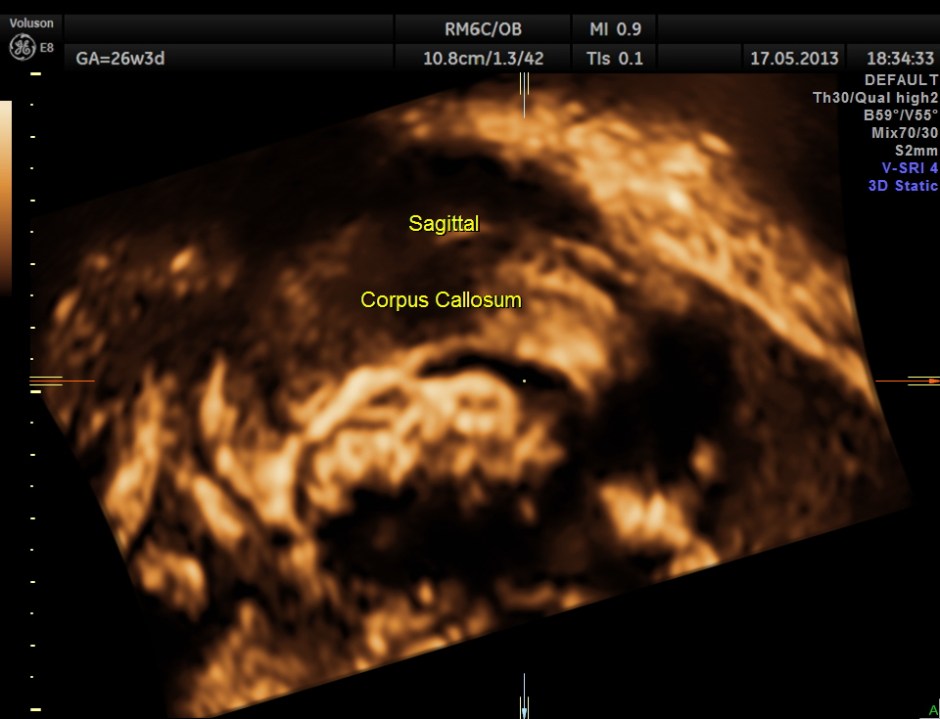

The following are 3 D reconstructed sagittal and coronal images .